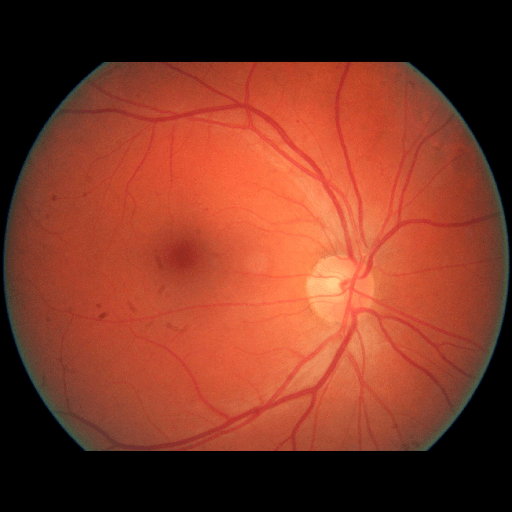

We conducted a case study on diagnosing diabetic retinopathy with ensembles of DL models. For benchmarking the performance of our ensemble-based solutions under the scheme described in Sec.3.3, we used two popular collections of diabetic retinopathy image data, the Kaggle Diabetic Retinopathy dataset [22] (hereafter referred to as “Kaggle-DR”) and the Messidor-2 dataset [23], each respectively consisting of and high resolution images. Diabetic retinopathy is graded into five SLs, as displayed in Figure 2. Following the problem setup used in previous papers [24], we trained models to distinguish the referable (SL2-4) cases from the non-referable ones (SL0 & SL1) (see Section B.1 for more detailed descriptions). We also tested our trained ensemble models on two o.o.d. image datasets (ImageNet [25] and CIFAR-10 [26]) to examine their capabilities of identifying o.o.d. inputs (see Section B in the supplementary materials).

The Kaggle-DR dataset comprises high resolution images. The presence of diabetic retinopathy is rated into five different SLs: no-DR (SL0), mild (SL1), moderate (SL2), severe (SL3), and proliferate (SL4), as illustrated in Figure 2. We divided the Kaggle-DR dataset into a development set and a test set, which respectively consisted of and images. The data in the development set were used to train and validate our Deep Learning (DL) models. The Messidor-2 dataset [38] that consisted of images was also used in our experiment as an additional dataset to test the true generalization performance of the models trained on the Kaggle-DR dataset. Images in Messidor-2 dataset were graded into the five SLs as in the Kaggle-DR dataset. Figure S.1 provides an illustration of the datasets used in our experiments.